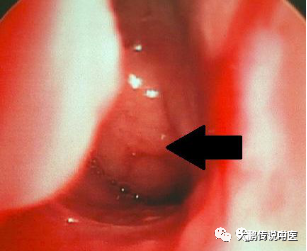

所以,详细的症状评估和检查是第一位的,如果孩子出现鼻塞,张口呼吸,打鼾、睡眠影响等问题,可以做检查。目前腺样体检查法包括间接鼻咽部触诊、鼻咽镜检查、鼻咽侧位X片。鼻内窥镜检查能够直接反映腺样体的大小、颜色、形态、是否压迫咽鼓管咽口及堵塞后鼻孔的面积,此检查安全性及诊断准确性较高。鼻咽部侧位X线片检查及鼻咽部CT检查,能够测量鼻咽气道阻塞程度,观察邻近骨质,易于鉴别诊断。

腺样体肥大不是一下就堵塞了,如果仅有一次急性感染,那么腺样体肿大通过治疗后,就逐渐恢复了,没啥大问题;但是如果长期反复的感染,那腺样体就会不停的受到刺激,出现过度的、持久的增生,就会阻塞鼻咽处,出现鼻塞、张嘴呼吸、打鼾等症状,就称为腺样体肥大了。